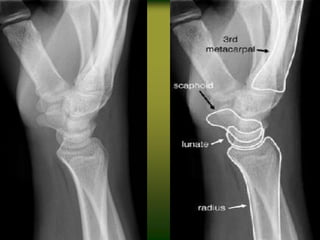

Bony

Anatomy

♦ Phalanges: 14

♦ Carpals

– Proximal row: 4

– Distal row: 4

♦ Radius and Ulna

Bony Anatomy ♦ Phalanges: 14 ♦Sesamoids: 2 ♦ Metacarpals: 5 ♦ Carpals – Proximal row: 4 – Distal row: 4 ♦ Radius and Ulna